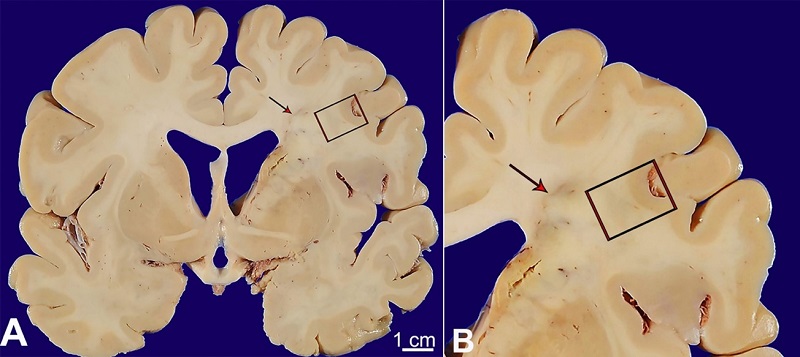

External examination of the brain and attached vessels revealed multifocal moderate to severe atherosclerosis, including severe disease in the communicating segment of the right internal carotid artery with approximately 90% stenosis. Serial coronal sections revealed multiple lesions scattered throughout the cerebral hemispheres concerning acute/subacute to chronic infarcts. The largest involved the caudal right hemispheric deep grey matter and medial temporal lobe, extended to the right occipital pole, including the calcarine sulcus and visual cortex and corresponded to the PCA territory infarct identified on antemortem imaging. Adjacent to, but not contiguous with the large PCA infarct, was a separate, well-demarcated wedge/”cigar-shaped” lesion involving the right deep white matter, extending from the frontal pole to the parieto-occipital lobe (Figure 2). Hematoxylin and eosin-stained tissue sections from this second lesion revealed a subacute infarct with central necrotic debris, neuronal loss, rarefaction, macrophage infiltration, neovascularization, axonal spheroids, and gliosis (Figure 3).

The case presented here provides radiologic and post-mortem documentation of an evolving IWI. Similarly to the patient’s reported clinical history, cardiovascular disease, and proximal carotid atherosclerotic disease are important risk factors for the development of internal watershed infarcts in addition to diabetes mellitus; however, smoking and hypertension have not been independently associated with IWI when compared to general stroke patients in one retrospective study.1 The pathogenesis of IWIs is thought to be secondary to hemodynamic instability and severe hypoperfusion,4-5 and the current findings support this hypothesis, showing bilateral white matter ischemic changes as well as right hemispheric IWI extension in the context of hemodynamic compromise secondary to a large PCA infarct. With respect to the patient’s incidental diagnosis of asymptomatic COVID-19, it is unclear whether this had any significant impact on his risk of ischemic stroke. Although some COVID-19 patients may suffer from hypercoagulability due to some, as yet, unknown mechanism, the incidence of ischemic stroke in COVID-19 patients is only about 2-3%, and most of these patients have conventional vascular risk factors, and mechanism of ischemic injury.8-9 Finally, the timeline of the development of a beaded pattern of IWI on radiographs four days post-admission, followed by the identification of a “cigar-shaped” IWI at autopsy nearly a month later, is supportive of the “rosary-like” pattern of IWI progressing to a confluent pattern over twenty-two days.

In addition to providing a unique pathologic-radiologic IWI, the case is instructive to autopsy practitioners. While superficial cortical watershed infarcts are well-known in autopsy pathology and major superficial watersheds are routinely sectioned at the time of brain cutting, the internal watershed is rarely a consideration at the time of autopsy. Failure to recognize the neuroanatomy corresponding to the internal watershed could lead to diagnostic confusion, such considering different, erroneous entities that may include demyelinating diseases or superimposed infections. Recognizing the pattern of IWIs facilitates accurate and succinct pathology correlation within the clinical context of hemodynamic instability and evolving ischemic insult.

No published example of a gross correlate to IWI was found on literature review using relevant search criteria pertaining to gross, histological, pathological, or neuropathological correlates to radiologically and clinically documented IWIs, and for this reason, the case stands as a helpful demonstration of this pattern of infarct for autopsy practitioners. The only major limitation of this case report is that only a single example of a well-documented gross representation of an IWI is reported.